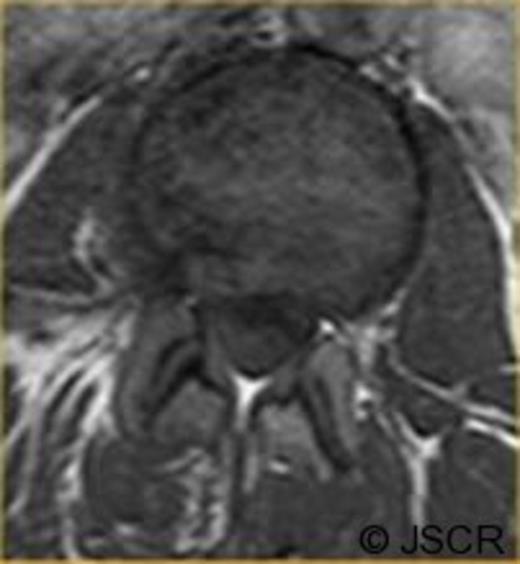

Magnetic Resonance Imaging scan (Fig. 1–4) showed L2/3 disc prolapse impinging on the right exit canal and causing L2 and L3 compression, thus she was listed for L2/3 lumbar discectomy and decompression. Examination of the right L2/L3 dermatomes revealed severe paresthesia and mild grade 4/5 weakness; reflexes were all normal. All other neurological examination was normal.

Preoperative axial T1 weighted image showing disc bulge at L2/3 to the right.